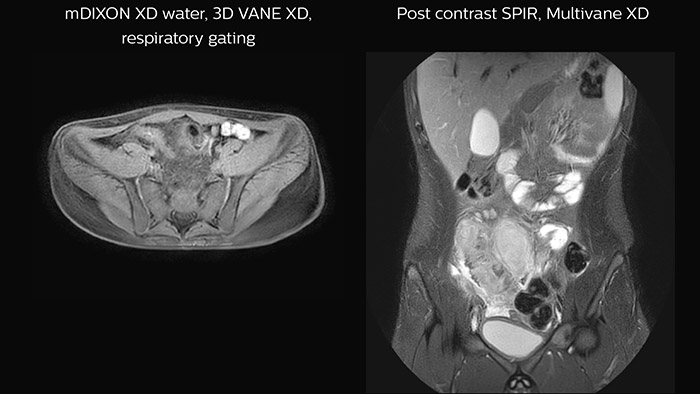

Crohn’s disease in the terminal ileum

A large abscess is visible near the terminal ileum, in the middle of the coronal image.